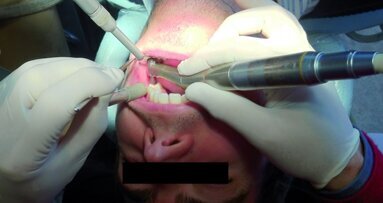

Les premières molaires (Fig. 7) sont étroitement associées au désir d’être reconnu dans la société comme dans la famille. L’atteinte des idéaux pour améliorer notre position dans la société est liée à la première molaire supérieure droite ainsi qu’à la première molaire inférieure droite, et ces dents reflètent notre vie professionnelle et notre réussite à cet égard. La patiente présentée à la figure 8 avait dû renoncer à sa passion professionnelle en raison de circonstances familiales qui l’avaient contrainte à déménager et demeurer chez elle. Après un traitement endodontique de la seconde prémolaire supérieure droite et de la première molaire supérieure droite (dents 15 et 16), elle a présenté une importante lésion périapicale de la dent 16 quelques années plus tard (Fig. 9). Elle n’avait probablement pas encore accepté sa nouvelle situation.